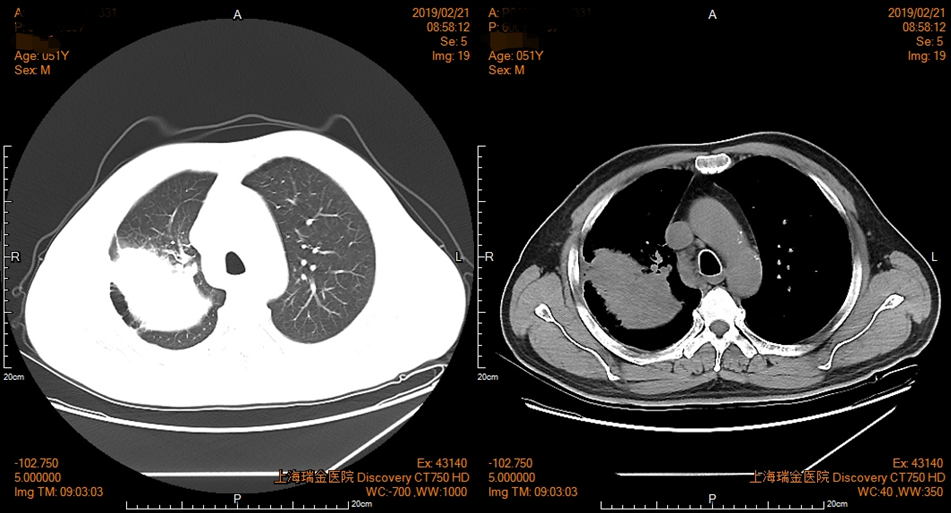

2019年2月21日胸部CT(薄层)增强(图):右肺上叶占位,大小9.1*6.1cm,邻近胸膜增厚,粘连,考虑恶性肿瘤,两肺上叶肺气肿,纵隔淋巴结增大。盆腔CT增强未见异常。

图1 患者胸部CT影像资料(2019年2月21日)